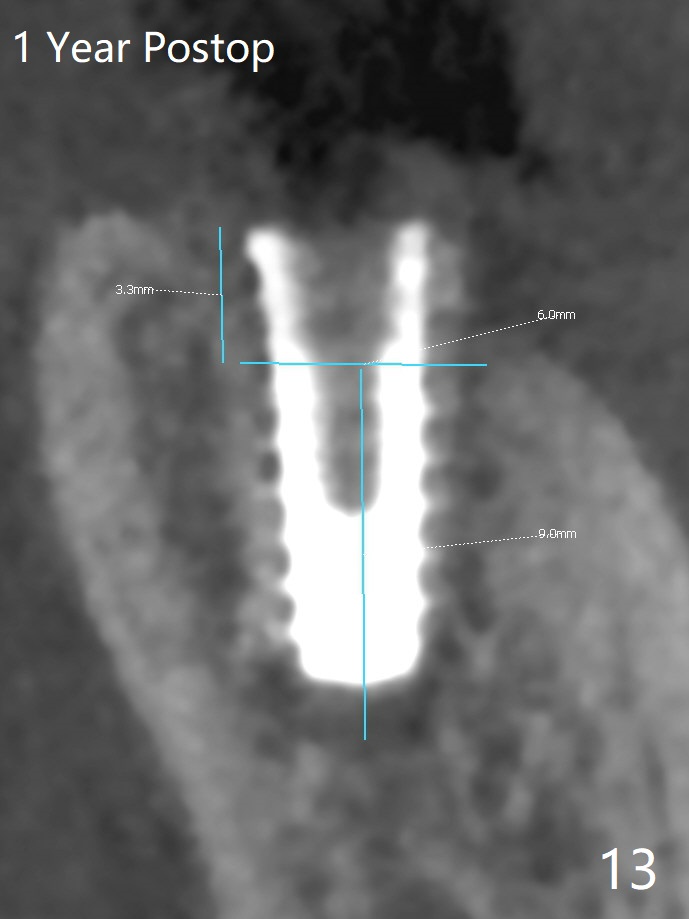

After placement of a 5x11 mm implant and cover screw at #18, allograft mixed with PRF (sticky bone) is placed in the peri-implant space, but it appears that bone density in the apical region (Fig.1 A) is lower than that in the coronal one (C) because of a constriction between the implant and the distal crest (*). Ideally the undercuts (Fig.2 *) of the extraction socket (black area) should be identified. Place bone graft in the undercuts (Fig.3 red circles) after osteotomy (white outlines) and before implant placement! A 4.5x1 mm temporary abutment is placed for an immediate provisional. The 2nd shortcoming of this case is that the implant is placed a little buccal. The papilla mesial to the immediate provisional (Fig.4 P) looks normal 4 days postop (no food impaction is expected when a final restoration is cemented). Additional acrylic (*) was placed to close a buccal gap when the provisional was seated with the temporary abutment. The patient reports loss of a piece of material in 4 days. It must be the additional acrylic, since it is absent 6 weeks postop (Fig.5). The provisional (Fig.5 P) looks wide, probably related to post-extraction gingiva and bone atrophy (Fig.6, 7 *). Bone graft (Fig.6 <) becomes a component of the gingival cuff. The provisional is re-trimmed for better oral hygiene. The gingival cuff is basically healthy 3.5 months postop, although the temporary abutment is loose and the implant is tender to rewinding and winding (Fig.8). The implant seems to remain non-osteointegrated 3.5 months postop (Fig.9). Although the bone density around the implant increases nearly 6 months postop (Fig.10), the implant remains tender when a 5x4(4) mm pair abutment is tightened. The healing abutment is reused. The bone density around the implant increases 11 months postop (Fig.11). Uncover is done with 5.5 mm profile drill. One month post uncover (12 months postop), the implant remains unstable (Fig.12). Prepare sticky bone x1. Make incision for exploration, including retightening the implant after Titanium brush and H2O2 Q-tip rubbing. If needed, a larger and shorter UF implant is a replacement (Fig.13). The implant is removed, cleaned with Titanium brushes and H2O2 in vitro and repositioned 12 months postop (Fig.14: arrow (gaps: post granulation tissue removal)). The gaps are regrafted with sticky bone and covered with PRF membrane and Cytoplast. Although the patient complains of severe pain the first 2-3 postop, the wound is apparently healing 12 days postop. The Cytoplast is exposed asymptomatic 5 weeks postop (Fig.16) and removed (Fig.17). The wound appears to have healed without loss of the bone graft (Fig.18).术后四个月伤口愈合,骨粉几乎没有丢失,有骨小梁形态(图十九:*)。切开,刮匙去骨,有一定硬度,即刻放置修复基台,完全就位(图二十),制备临时牙冠,牙周敷料固定组织瓣(没有缝线)。